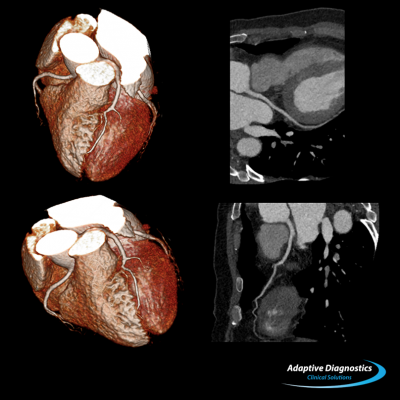

Cardiac CT image of a patient with atrial fibrillation using the Sure Cardio prospective arrhythmia detection software.

- Sure Cardio: Prospective with arrhythmia detection is a unique application that dramatically lowers patient dose during coronary CTA exams using a helical acquisition technique to provide one continuous image instead of multiple images. It automatically detects and adjusts to patients with irregular heartbeats, providing quicker, more conclusive exam results.